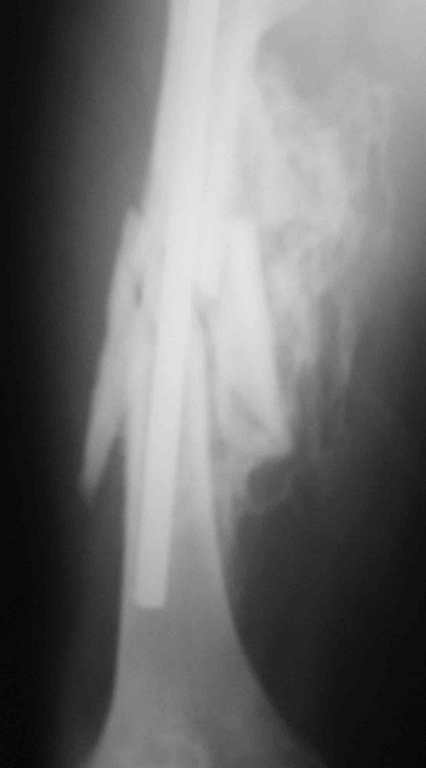

[Ortho] 32- летний пациент с переломами обоих бедер после неудачного оперативного и консервативного лечения.

Имя     : fem R.jpg